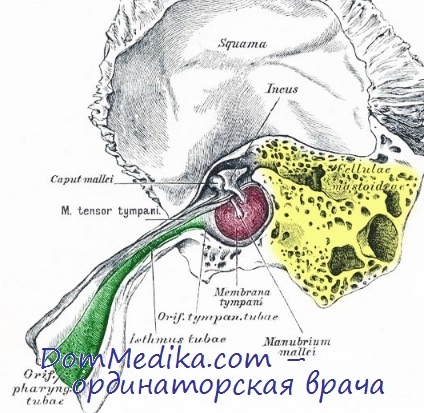

КТ анатомия сосцевидного отростка: особенности и показания